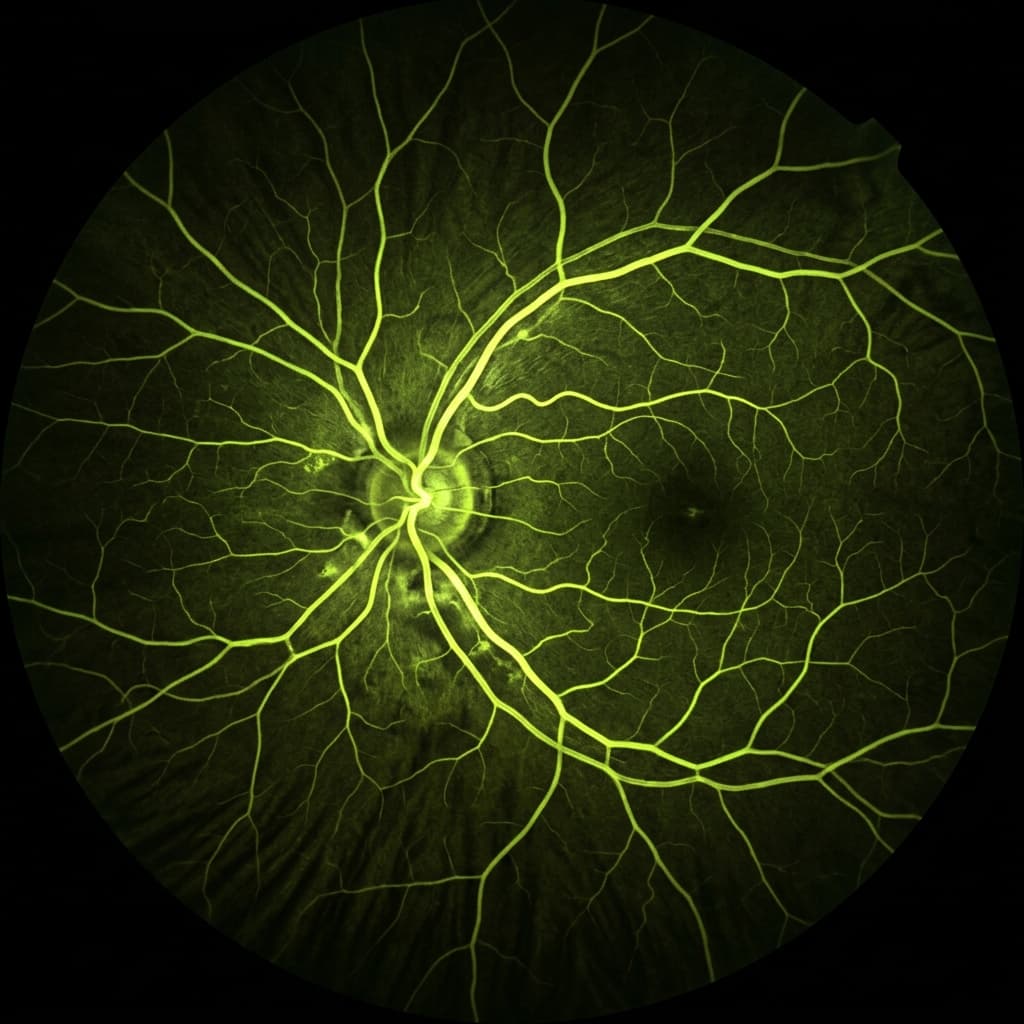

Fluorangiografía retiniana

Estudio especializado con medio de contraste para evaluar detalladamente la circulación sanguínea en la retina.